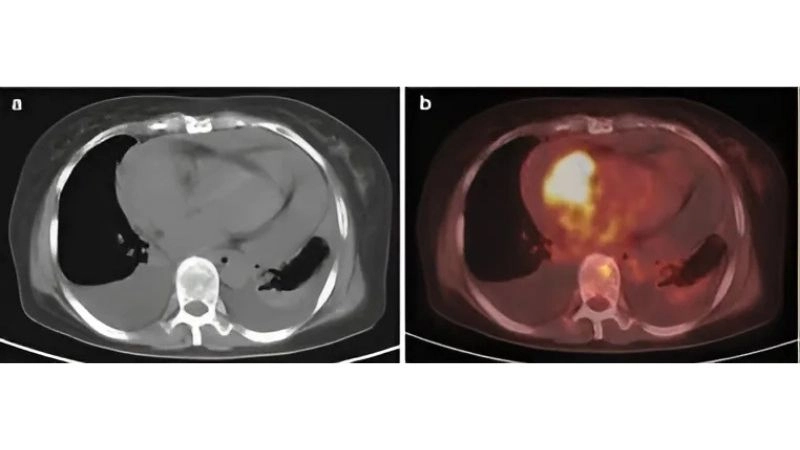

Images visual examples of cardiac sarcoma

Cardiac sarcoma is a rare malignant tumor that originates in the heart’s tissues, disrupting circulation and heart function. Visual examples often include MRI or CT images showing irregular masses within cardiac chambers.